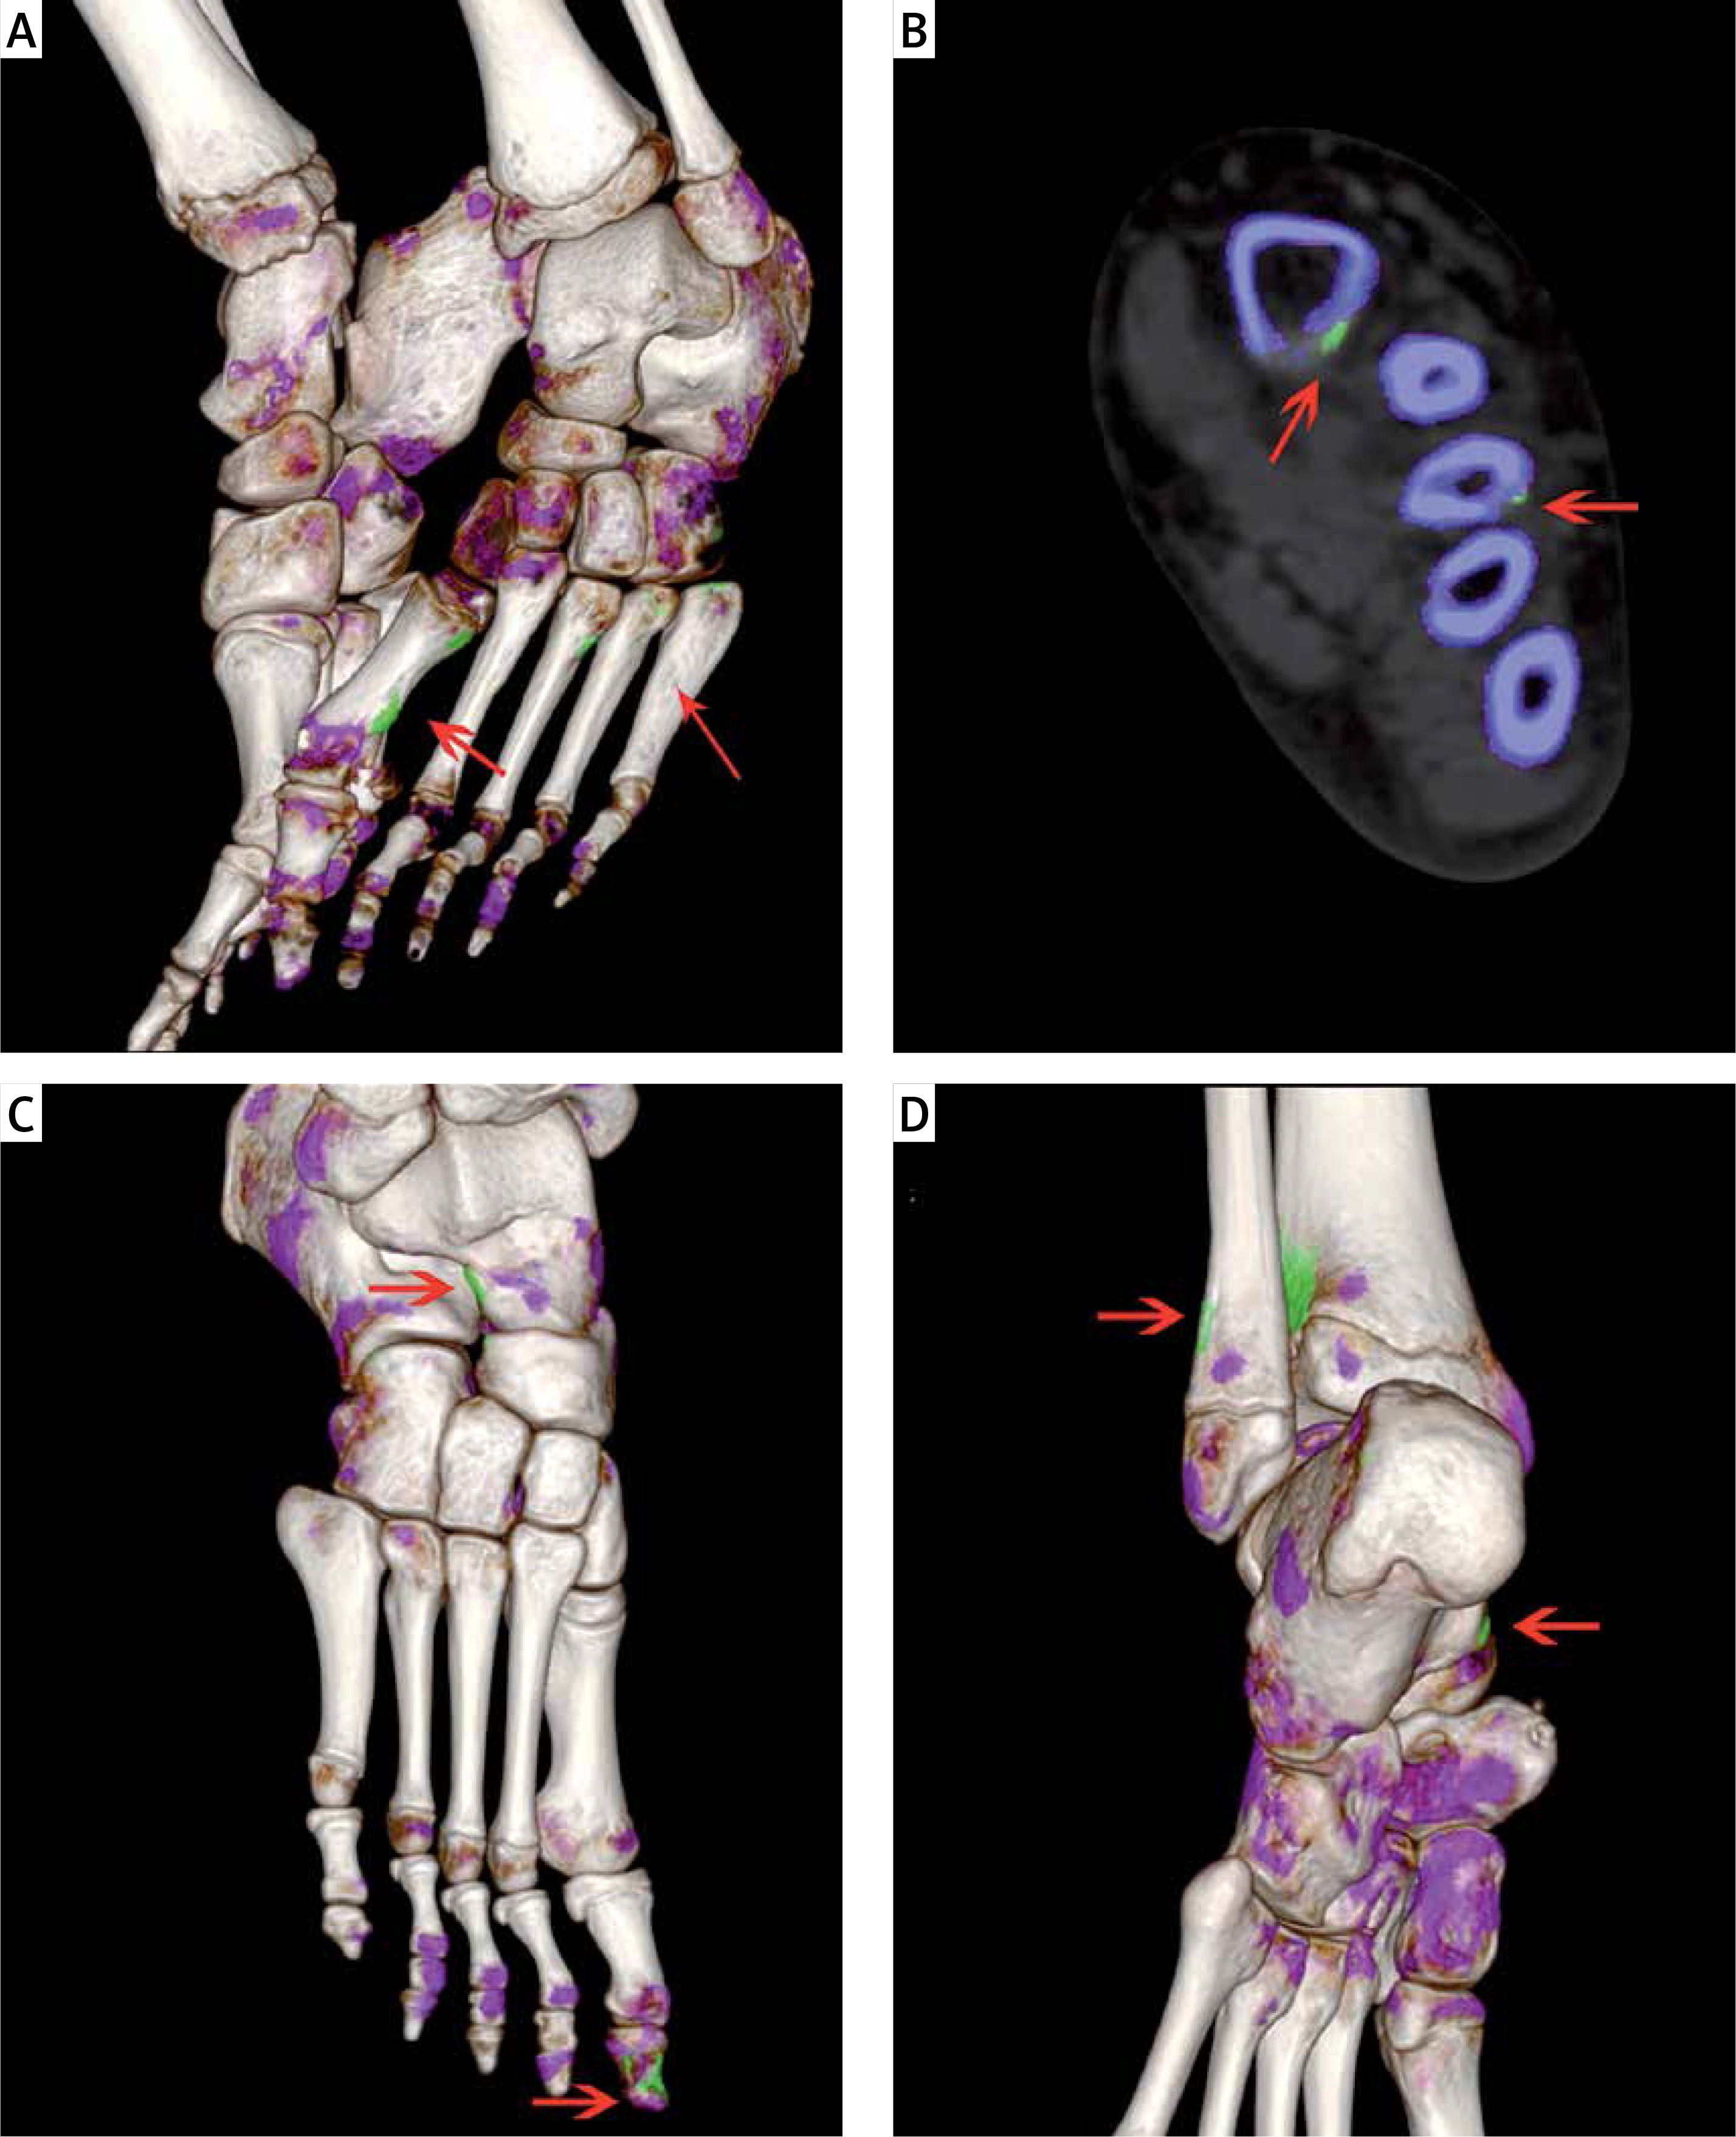

In the Joint Group, DECT MSU deposits were found in 28 (84.8%) children, and 14 (60.9%) children in the Asymptomatic Group (Table I). In total, 99 areas of urate deposition were observed in all participants. We found 60 areas of urate deposition in the Joint Group; DECT urate crystal deposition was most frequently observed in the first metatarsophalangeal (MTP) joint (30.0%), ankle joint (15.0%), and calcaneus (13.3%). Ninety-nine areas of urate deposition were found in the Asymptomatic Group; DECT urate crystal deposition was most frequently observed in the calcaneus (25.6%), the first MTP joint (17.9%), and the first phalanx (15.4%) (Table II, Figure 1).

Figure 1

A, B – 10-year-old boy, HUA with left foot hallux swelling and pain. A – Three dimensional fusion, B – two dimensional coronal images show MSU crystal deposits (green) of the left metatarsals (arrows), and bone erosion. C, D – 10-year-old girl, asymptomatic HUA: C – the right foot, D – the left foot. Three dimensional fusion images show MSU crystal deposits of the right navicular bone, the right first metatarsal and lower end of left tibia and fibula, left calcaneus